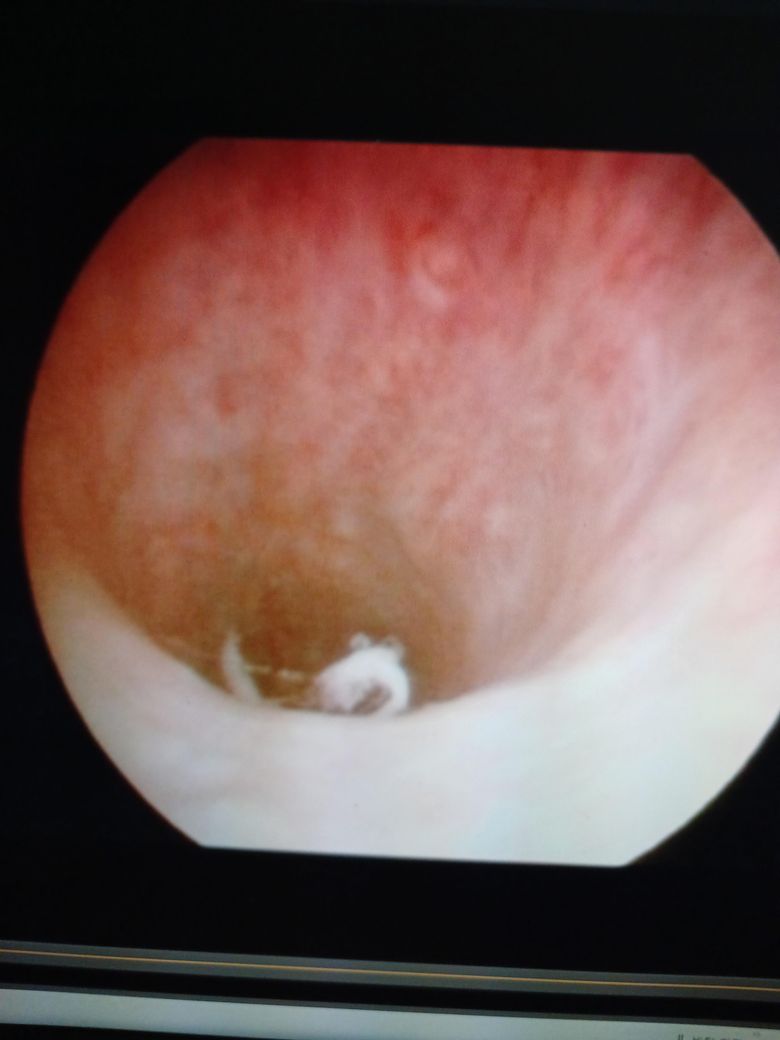

제가 사진을 보내준다고 했는데 사진을 보내 드리지 못했습니다. 방광 내시경을 했는데 껍질이 좀 벗겨 나갔습니다. 껍질이 벗겨 나간 부위에 만약에 이물질이 붙어? 있다면 소변으로 나올 수

제가 알고 싶은 것은 껍질이 나간 엠브이에 이물질이 달라붙으면 그 이물질이 함께 굳어질 수가 있는지요제가 알고 싶은 것은 껍질이 나간 MV에 이물질이 달라붙으면 그 이물질이 함께 굳어질 수가 있는지요.

이물질제가 알고 싶은 것은 껍질이 나간 부위에 이물질이 달라붙으면 그 이물질이 함께 굳어질 수가 있는지요.

방광은 일반적으로 소변만 들어있습니다. 벗겨진 점막에 이물질이 붙어있을 수 없습니다.

점막이 재생되는데 걸리는 시간은 사람마다 다르지만, 평균적으로 일주일정도면 재생이 완료가 됩니다.

벗겨진 상태의 점막은 소변으로 정상적으로 배출이 됩니다.